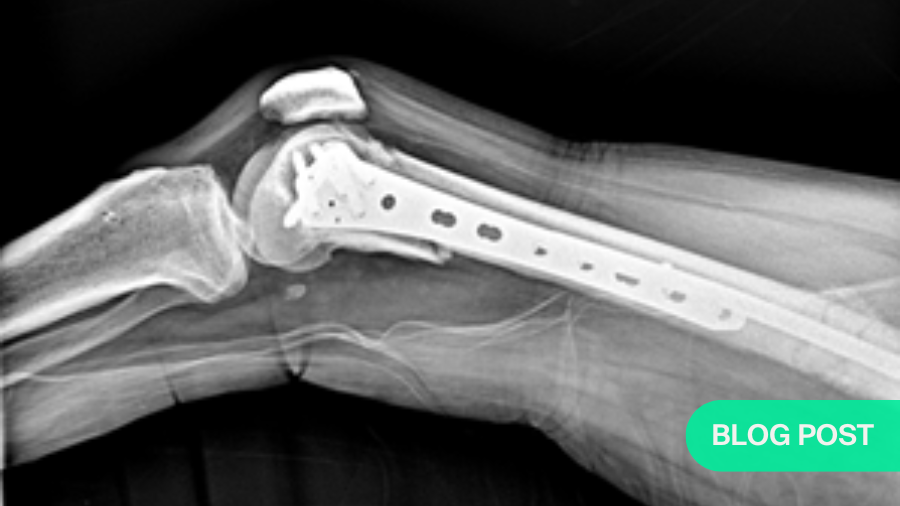

As seen in the following images, all fracture sites healed with near-complete functional recovery, and no complications or deficits were reported. The full clinical case, including a video demonstrating the patient's functional recovery, can be accessed via this link.

The patient remained non-weight bearing for the first month post-surgery and immediately began physiotherapy to restore hip and knee range of motion and strengthen the quadriceps and gluteal muscles bilaterally.

Progressive weight-bearing was allowed afterward, as tolerated, until full weight-bearing was achieved.